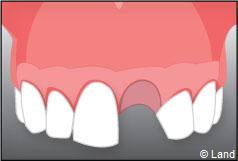

– le remplacement d’une dent unitaire. Grâce à ce procédé, il n’y a pas de mutilation des dents voisines.

Exemple d’un implant unitaire pour remplacer une dent antérieure manquante.